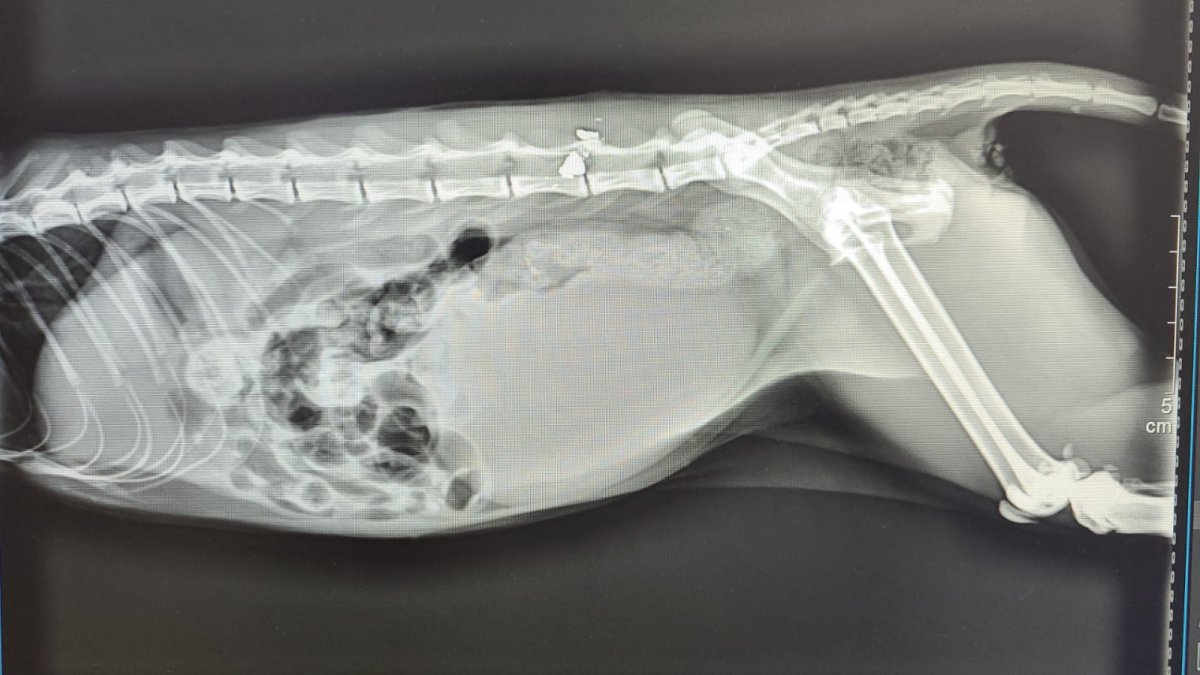

Radiografía del animal.

El animal fue trasladado de inmediato a una clínica veterinaria donde, tras realizarle todas las pruebas médicas, estas concluían que se trataba de una grave lesión ocasionada por un balín en la columna vertebral. Algo que demuestra la poca humanidad de las personas que realizan este tipo de actos y que debemos vigilar”.